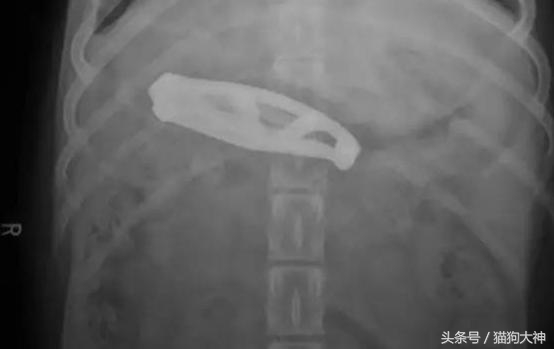

这只狗狗趁主人不关注,吞下了一把折叠刀,发现不对的主人赶紧送它去了医院。

所幸主人把不用的小刀折叠好了,狗狗并没有什么大碍。

但狗狗傻起来简直让人目瞪口呆,这只狗狗竟然吞下了一把这么长的刀!不是所有狗狗都有能化险为夷的好运气,所以就需要主人留心帮它们排除生活在可能存在的危险。